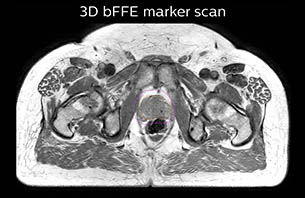

Using the mDIXON and 3D bFFE images, the RT planner marks the position of the nickel-titanium fiducial markers, and contours are transferred to the digitally reconstructed radiographs (DRRs). Reference image matching is based on these markers. “In the rare cases, where visualization of the fiducial markers fails, we do a CT to confirm their location,” Dr. Keyriläinen notes.

The 3D T1W FFE mDIXON sequence provides in-phase, water and fat images in one acquisition. Target and organs-at-risk are delineated on the 3D T2W TSE images. Prostate GTV is shown in orange, PTV in purple. The 3D bFFE sequence is used by the planner to mark the position of the fiducial markers (gold anchors) and contours are transferred to the digitally reconstructed radiographs (DRRs).